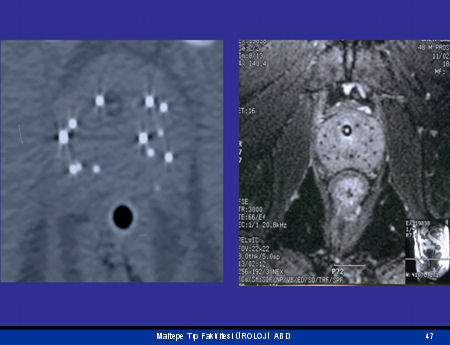

Ultrason: Hem prostat kanserini gösterme hem de yayılma derecesini anlamada önemli bir tetkiktir. Ultrason karından yapılabileceği gibi aşağıdaki resimde görüldüğü gibi makattan yapılabilmekte “trans rektal ultrasonografi TRUS“ ve prostat kanseri ve kanserin prostat dışına yayılımı net olarak görülmektedir. TRUS ayrıca görerek biyopsi almada da kullanılır. Ultrason probundan sokulan otomatik iğneler yardımı ile kanserli alandan kontrollü bir şekilde değişik sayıda ( 8-12 kadrandan ) parça almak mümkündür. Prostat kanserinden şüphelenildiği zaman iğne ile prostattan parça alınıp patolojide incelenilir.

Bilgisayarlı Tomografi ve MR: Ultrasonografi gibi prostat kanserini gösterme ve özellikle lenf bezlerine olan yayılma derecesini anlamada kullanılırlar. PSA değeri > 20 ng/ml olan hastalarda yaptırılması tavsiye edilmektedir.